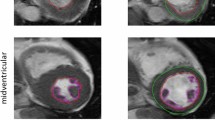

Deep learning algorithms for left ventricle (LV) segmentation are prone to bias towards the training dataset. This study assesses sex- and age-dependent performance differences when using deep learning for automatic LV segmentation. Retrospective analysis of 100 healthy subjects undergoing cardiac MRI from 2012 to 2018, with 10 men and women in the following age groups: 18–30, 31–40, 41–50, 51–60, and 61–80 years old. Subjects underwent 1.5 T, 2D CINE SSFP MRI. 35 pathologic cases from local clinical exams and the SCMR 2015 consensus contours dataset were also analyzed. A fully convolutional network (FCN) similar to U-Net trained on the U.K. Biobank was used to automatically segment LV endocardial and epicardial contours. FCN and manual segmentation were compared using Dice metrics and measurements of end-diastolic volume (EDV), end-systolic volume (ESV), mass (LVM), and ejection fraction (LVEF). Paired t-tests and linear regressions were used to analyze measurement differences with respect to sex and age. Dice metrics (median ± IQR) for n = 135 cases were 0.94 ± 0.04/0.87 ± 0.10 (ED endocardium/ES endocardium). Measurement biases (mean ± SD) among the healthy cohort were − 0.3 ± 10.1 mL for EDV, − 6.7 ± 9.6 mL for ESV, 4.6 ± 6.4% for LVEF, and − 2.2 ± 11.0 g for LVM; biases were independent of sex and age. Biases among the 35 pathologic cases were 0.1 ± 19 mL for EDV, − 4.8 ± 19 mL for ESV, 2.0 ± 7.6% for LVEF, and 1.0 ± 20 g for LVM. In conclusion, automatic segmentation by the Biobank-trained FCN was independent of age and sex. Improvements in end-systolic basal slice detection are needed to decrease bias and improve precision in ESV and LVEF.